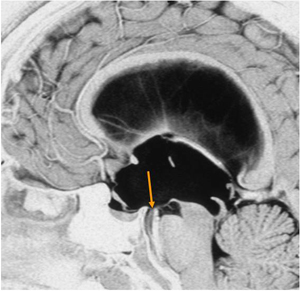

図3.非交通性水頭症の様子

矢印の場所が開窓を行う第3脳室の床です。

シャントでは管が詰まってしまえば急に具合の悪くなることがあったり、流量の調節がうまくいかず脳と骨の間に血液がたまってしまったりする場合があります。第3脳室底開窓術は神経内視鏡を用いて第3脳室の床(図3)に小孔を開けて風船着きのカテーテルで拡大する手術(図4)で、シャントの管などの異物を頭の中に残さず、より生理的な髄液の循環状態にすることができます。第3脳室底開窓術はこのようにメリットも多いのですが、神経内視鏡という新しい器具を用いるので、慣れた人にしていただくことがとても大切で、当院は100例を超える経験があり安心して手術を受けられます。